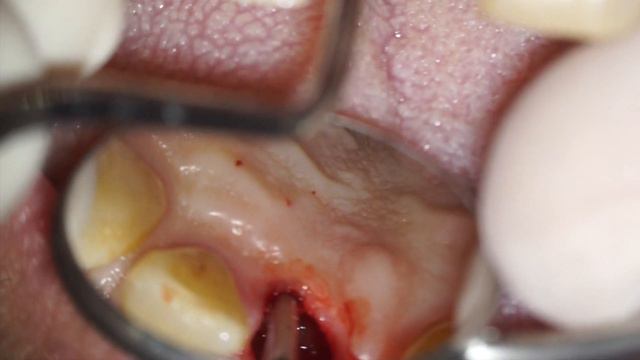

Atraumatic Root Extraction by means of an endodontic file - Dr Fabio Cozzolino смотреть онлайн

02:09

Atraumatic Root Extraction by means of an endodontic file - Dr Fabio Cozzolino

Secretive Adventures 16 просмотров